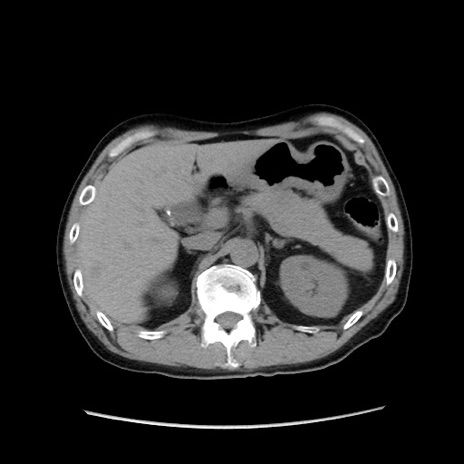

症例37(横断像)

【症例】40歳代 男性

【主訴】腹痛

【現病歴】4時間ほど前に電車に乗車中に臍部上より腹痛出現。徐々に増悪し起立困難となり、救急外来受診。生ものは数日食べていない。今朝お雑煮を食べた。

【身体所見】BT 36.8℃、BP 117/84mmHg、HR 91/min、SpO2 97%、苦悶様、腹部:臍上部広範囲圧痛あり、反跳痛±

【データ】WBC 8100、CRP 0.03